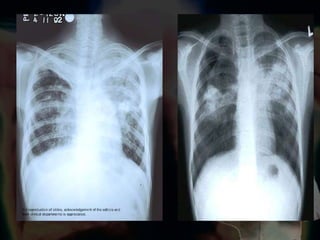

Manifestaciones Radiográficas

Tuberculosis Primaria Progresiva SNC Medula ósea Huesos   riñones Sistema  linforeticular Serosas   Órganos afectados Radiografía  Infiltrados de ocupación alveolar.  Crecimiento ganglionar regional

Órganos afectados Ganglios linfáticos SNC Las serosas  El  riñón Las glándulas suprarrenales Las articulaciones Los huesos Radiografía  Lesiones cavitarias acompañadas de fibrosis Retracciones de localización apical Cavernas de paredes gruesas: infiltrados mixtos